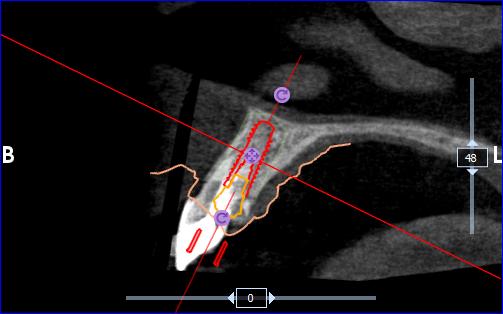

• Bilan 3D ou Tomographie volumique à faisceau conique ou Cone Beam Computed Tomography (Photo 4)

Sur le cone beam réalisé nous retrouvons bien notre lésion latérale au niveau de 11 et notre lésion apicale au niveau de 21. A noter également la fracture palatine du tiers cervical radiculaire.

On note la présence d’une paroi osseuse vestibulaire intacte permettant d’envisager une extraction

atraumatique suivie d’une implantation immédiate, dans de bonnes conditions.

Le CBCT réalisé (fichiers dicom) est inséré dans le logiciel RealGuide pour permettre de l’associer avec

l’empreinte numérique de la patiente (Photo 8). Ces éléments nous permettent donc de simuler :

• L’avulsion de la dent 11

• L’évaluation des parois osseuses résiduelles

• La position implantaire idéale, en respectant l’axe prothétique et les contraintes anatomiques.